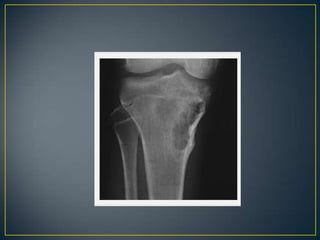

• Benign tumors and tumor-like bone lesions usually do not

exhibit soft-tissue extension; thus, almost invariably, a

soft-tissue mass indicates an aggressive lesion and one

that is in many instances malignant .

• With few exceptions—such as giant cell

tumors, aneurysmal bone cysts, osteoblastomas, or

desmoplastic fibromas.

• In the case of a bone lesion associated with a soft-tissue

mass, it is always helpful to determine which condition

• Although it is sometimes very difficult to distinguish

benign from malignant bone lesions on the basis of

radiography alone, certain characteristic features

favour one designation over the other.